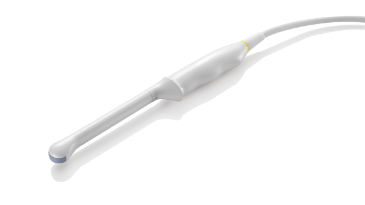

TecnologĂa de transductor 3T

con Cristal ?nico

Proporcionando imĂĄgenes mĂĄs nĂtidas, todas las sondas compatibles con el M9 vienen equipadas con la tecnologĂa de transductor 3T Ășnica de Mindray. Mejorado con el a?adido de la tecnologĂa de cristal Ășnico, el M9 ofrece una mejor penetraciĂłn y flujo dinĂĄmico de color, especialmente durante escaneado de pacientes difĂciles.